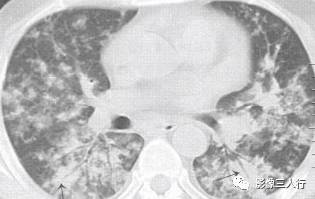

非典型肺炎的CT征象特点:分布不均匀、形态不同、大小不一的肺实变是本组 患者共同存在的基本CT表现。肺实变通常由于肺泡内充盈浆液性、渗出性或血性液 体、炎细胞或其他成分,导致肺实质弥漫性或局灶性密度增高。早期表现为边界不 清楚的0.5〜1.0cm的结节性高密度灶,随着病变的进展,融合成团块或斑片状阴 影,掩盖肺血管纹理。较大的实变影像内可见支气管分支的透亮影则为空气支气管征。见图9。